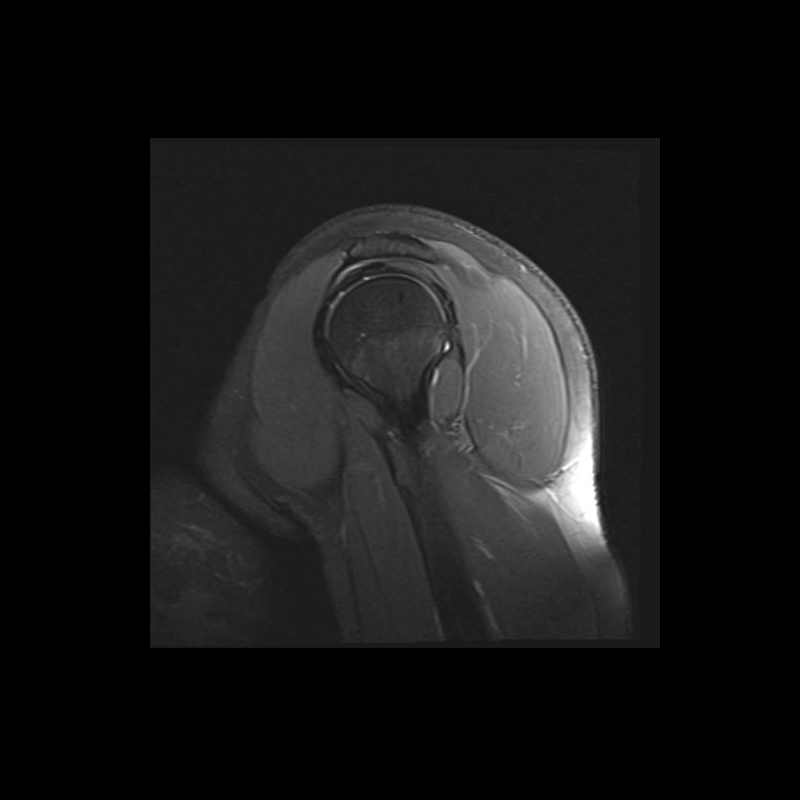

Shoulder MRI Anatomy